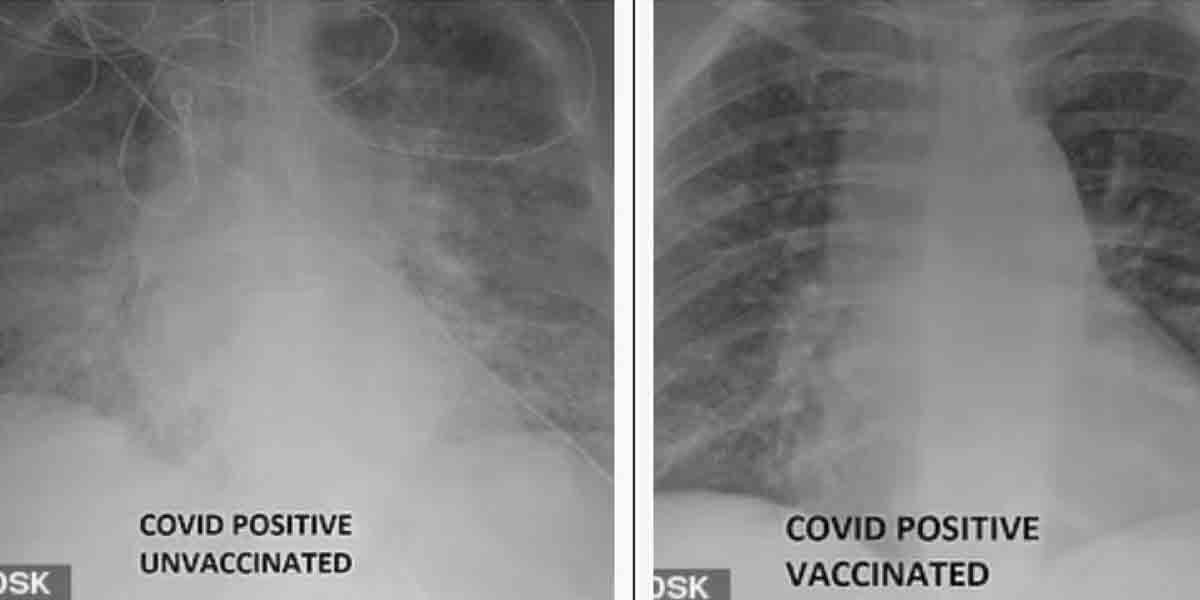

వ్యాక్సిన్ ఎందుకు తీసుకోవాలి? ఈ ఎక్స్రేలు ఏం చెబుతున్నాయ్? | ప్రపంచాన్ని కరోనా మహమ్మారి ఇంకా వెంటాడుతున్నది.. కొవిడ్ వ్యాప్తికి అడ్డుకట్ట వేసేందుకు వ్యాక్సినే ఆయుధమని నిపుణులు స్పష్టం చేస్తున్నారు..